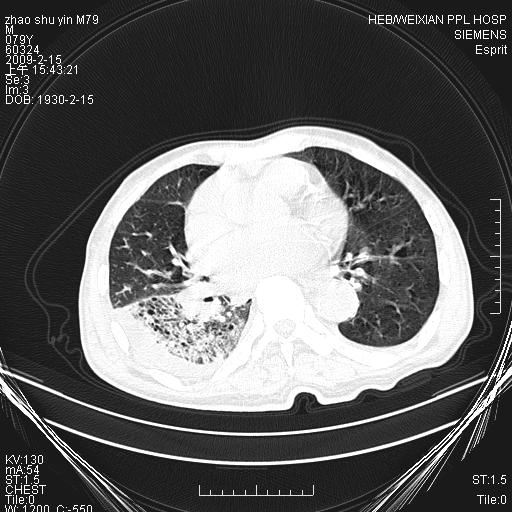

标题: CT18303:M79Y,右下肺病变

主因高热、寒战4天,伴有咳嗽,腹痛。

1。右下肺磨玻璃及蜂窝影考虑炎症 建议抗炎治疗后复查

2。右侧胸膜增厚 、右侧包裹性积液

3。心影增大 ,左心房增大为甚

4。右下肺门饱满(肿大淋巴结)